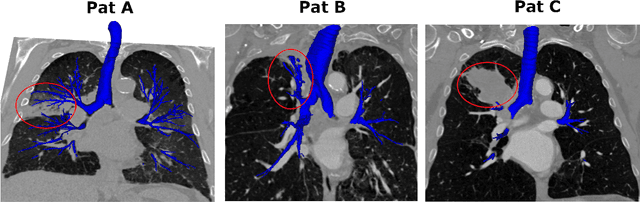

Abstract:To improve the prognosis of patients suffering from pulmonary diseases, such as lung cancer, early diagnosis and treatment are crucial. The analysis of CT images is invaluable for diagnosis, whereas high quality segmentation of the airway tree are required for intervention planning and live guidance during bronchoscopy. Recently, the Multi-domain Airway Tree Modeling (ATM'22) challenge released a large dataset, both enabling training of deep-learning based models and bringing substantial improvement of the state-of-the-art for the airway segmentation task. However, the ATM'22 dataset includes few patients with severe pathologies affecting the airway tree anatomy. In this study, we introduce a new public benchmark dataset (AeroPath), consisting of 27 CT images from patients with pathologies ranging from emphysema to large tumors, with corresponding trachea and bronchi annotations. Second, we present a multiscale fusion design for automatic airway segmentation. Models were trained on the ATM'22 dataset, tested on the AeroPath dataset, and further evaluated against competitive open-source methods. The same performance metrics as used in the ATM'22 challenge were used to benchmark the different considered approaches. Lastly, an open web application is developed, to easily test the proposed model on new data. The results demonstrated that our proposed architecture predicted topologically correct segmentations for all the patients included in the AeroPath dataset. The proposed method is robust and able to handle various anomalies, down to at least the fifth airway generation. In addition, the AeroPath dataset, featuring patients with challenging pathologies, will contribute to development of new state-of-the-art methods. The AeroPath dataset and the web application are made openly available.